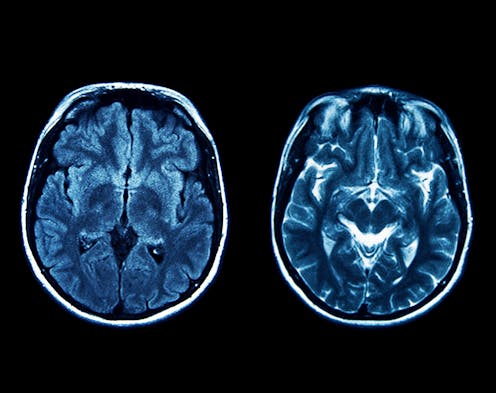

Huntington’s disease is caused by a mutation in the gene that makes a protein called huntingtin. The mutation makes the protein bigger and more likely to clump together. It is this increased stickiness that scientists believe causes brain cells to die in people with Huntington’s disease. As the disease progresses, it affects movement, learning, thinking and emotions.

These diseases share some of the characteristics of Huntington’s disease and spinal muscular atrophy, such as the accumulation of sticky proteins (although the actual proteins that build up are different). As with Huntington’s disease, there aren’t any drugs that slow down or halt the brain cells dying in people with Alzheimer’s or Parkinson’s.